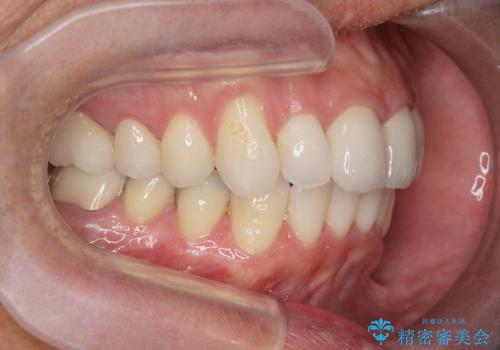

- 突き出た前歯の角度の改善と虫歯治療の改善を求めて来院されました。

虫歯を除去したのち、マウスピース矯正治療を行い、歯並びやがたつきを改善したのち、セラミックに置き換えることで審美性の向上を計画します。

矯正や虫歯治療、セラミック治療といった複合的な治療を一医院で行うことができるのが当法人の大きな特長です。